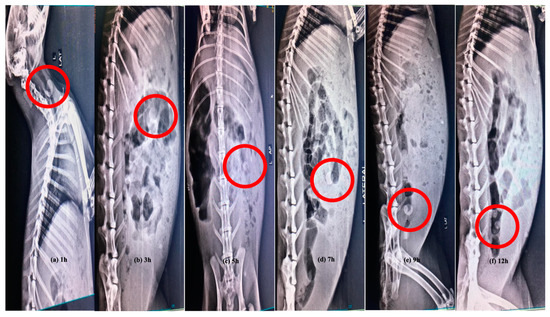

3.12. In Vivo X-ray Study